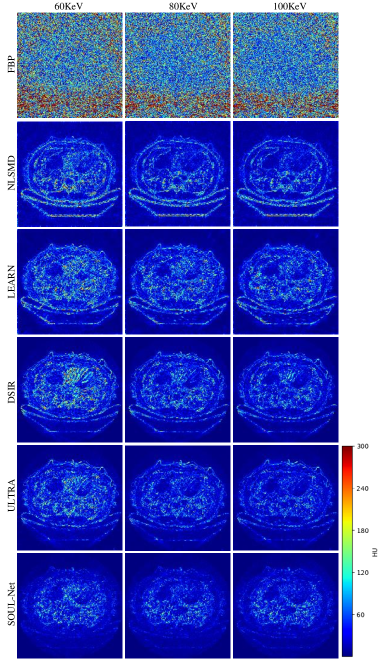

To better demonstrate the merits of SOUL-Net, Fig. 7 shows the absolute difference images associated with the reference image. It is obvious that our proposed SOUL-Net has minimal errors compared to other methods, which further confirms the effectiveness of our proposed method in noise and artifact suppression.

To further analyze the noise in the results of different methods in different frequency bands, the NPS maps are drawn in Fig. 8. It is clear that the proposed SOUL-Net outperforms all other methods in noise suppression.